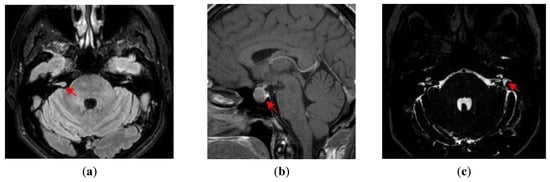

- (c)

- Menière’s disease (left ear): low-frequency sensorineural hearing loss, spontaneous episodes of vertigo (each lasting between 20 min and 12 h), fluctuating aural symptoms (hearing, tinnitus and fullness) in the affected ear, and saccular hydrops detected by 3D FLAIR MRI evaluation;